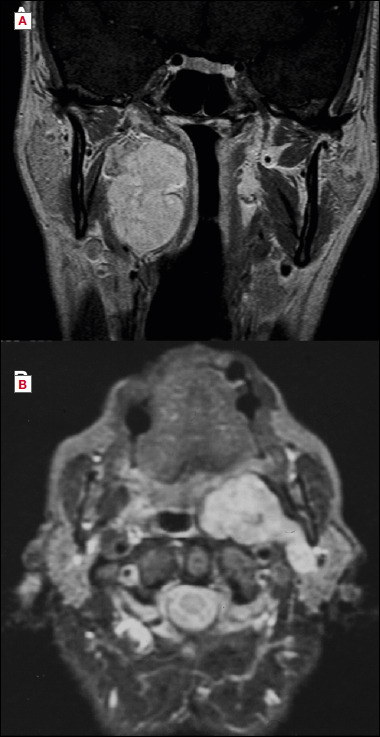

目的:探讨显微外科入路治疗咽旁间隙(PPS)肿瘤的安全性和有效性。第二个目的是评估术前和术后最终组织病理学诊断之间的对应关系。方法:对1985年至2022年间在2个三级转诊中心采用显微外科颈腮腺入路治疗的连续系列原发性PPS肿瘤进行分析。样本包括94例患者的97个肿瘤(88个良性和9个恶性),其中11例在我们中心首次诊断时患有复发性肿瘤。手术入路,根据假定的术前诊断,是包膜和整体切除(包括保守或根治性切除PPS)。结果:在97个肿瘤中,有88个肿瘤被完全切除。PPS显微手术后复发8例(多形性腺瘤4例,恶性神经鞘瘤2例,黑色素瘤1例,血管外皮细胞瘤1例)。8例复发病例中有4例在我们中心首次发现时是复发病例。术前诊断与最终组织学完全一致只发生在良性病变组,如副神经节瘤、神经鞘瘤或脂肪瘤,并行包膜切除。结论:显微外科手术可以通过狭窄的手术通道增加手术空间,改善对关键切割面、血管和神经的剥离,并允许显露病变的尾侧和颅侧范围,从而支持经颈腮腺入路。在我们的研究中,包膜和整体切除PPS对大多数患者都是有效的。在高级别恶性肿瘤中,除PPS壁外更广泛切除的病变可能包括血管和神经,应准确平衡适应证。

Objective: To investigate safety and efficacy of the microsurgical approach to parapharyngeal space (PPS) tumour. A secondary goal was to evaluate the correspondence between preoperative and final histopathologic diagnosis after surgery.

Methods: A consecutive series of primary PPS tumours treated between 1985 and 2022 in 2 tertiary referral centres with a microsurgical cervico-parotid approach was considered. The sample included 97 tumours (88 benign and 9 malignant) in 94 patients, of which 11 affected by recurrent tumours when first diagnosed at our centres. The surgical approaches, planned on the presumptive preoperative diagnosis, were pericapsular and en bloc resections (including either conservative or radical resections of the PPS).

Results: Pericapsular and en bloc resections of the PPS achieved complete removal in 88 out of 97 tumours. Relapses after PPS microsurgery occurred only in 8 cases (4 pleomorphic adenomas, 2 malignant schwannomas, one melanoma, and one haemangiopericytoma). Four of the 8 relapsed cases were recurrent cases when first seen at our centres. A complete correspondence between preoperative diagnosis and final histology occurred only in the group of benign lesions classified as paraganglioma, schwannoma, or lipoma, submitted to pericapsular resection.

Conclusions: Microsurgery may support the transcervical-parotid approach, by enhancing the operative space through narrow surgical corridors, improving dissection on critical cleavage planes, vessels and nerves, and allowing the exposure of both caudal and cranial extent of the lesions. In our series, pericapsular and en bloc resections of the PPS were effective in most of the included patients. In high-grade malignancies, where the morbidity of a wider resection beyond the PPS walls may include vessels and nerves, the indication should be accurately balanced.